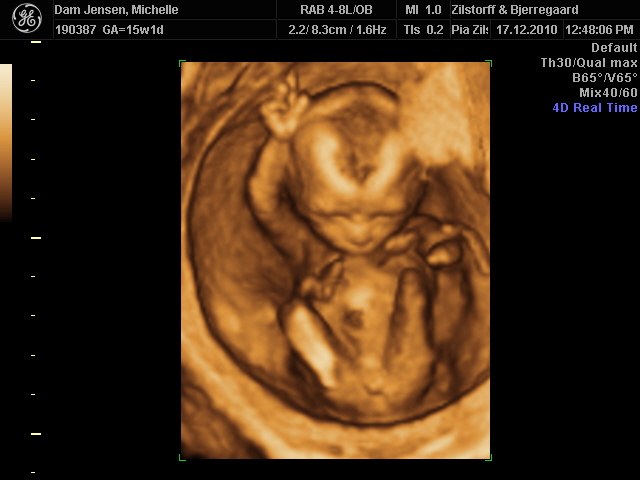

Det var så fantastisk at se hende i 3D selvom jeg ikke var længere henne end 15+1

men vægt mæssigt er hun 15+3 hehe så hun spiser godt må man sige

Alt var perfekt, hjerter, nyre, kranie tarme osv.. så vi var super stolte og glade